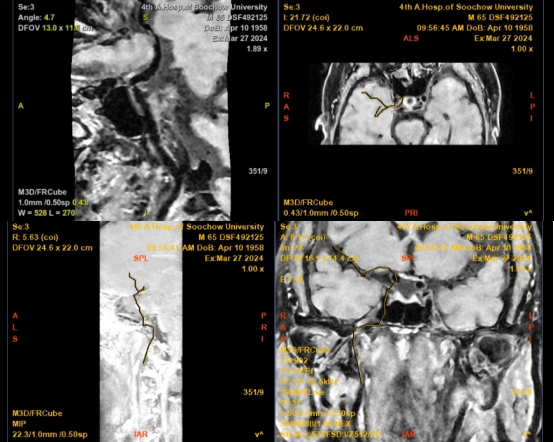

DSA:右侧大脑中动脉M1段管壁不规则溃疡斑块形成,局部重度狭窄

MRI平扫+增强:右侧大脑中动脉M1段远端不稳定斑块并管腔重度狭窄

患者再次入院后,郝永岗教授等专家合作完成苏州市首例术中磁共振指导下的症状性颅内动脉狭窄支架植入术。此次手术充分利用我院复合手术室(DSA+MRI双杂交)的优势,有效提高了手术的安全性和有效性。术后即刻行MRI-PWI显示:责任血管供血区血流灌注较前明显改善,提示支架精准定位释放。

术后DSA:右侧大脑中动脉未见明显残余狭窄,远端分支未见残端